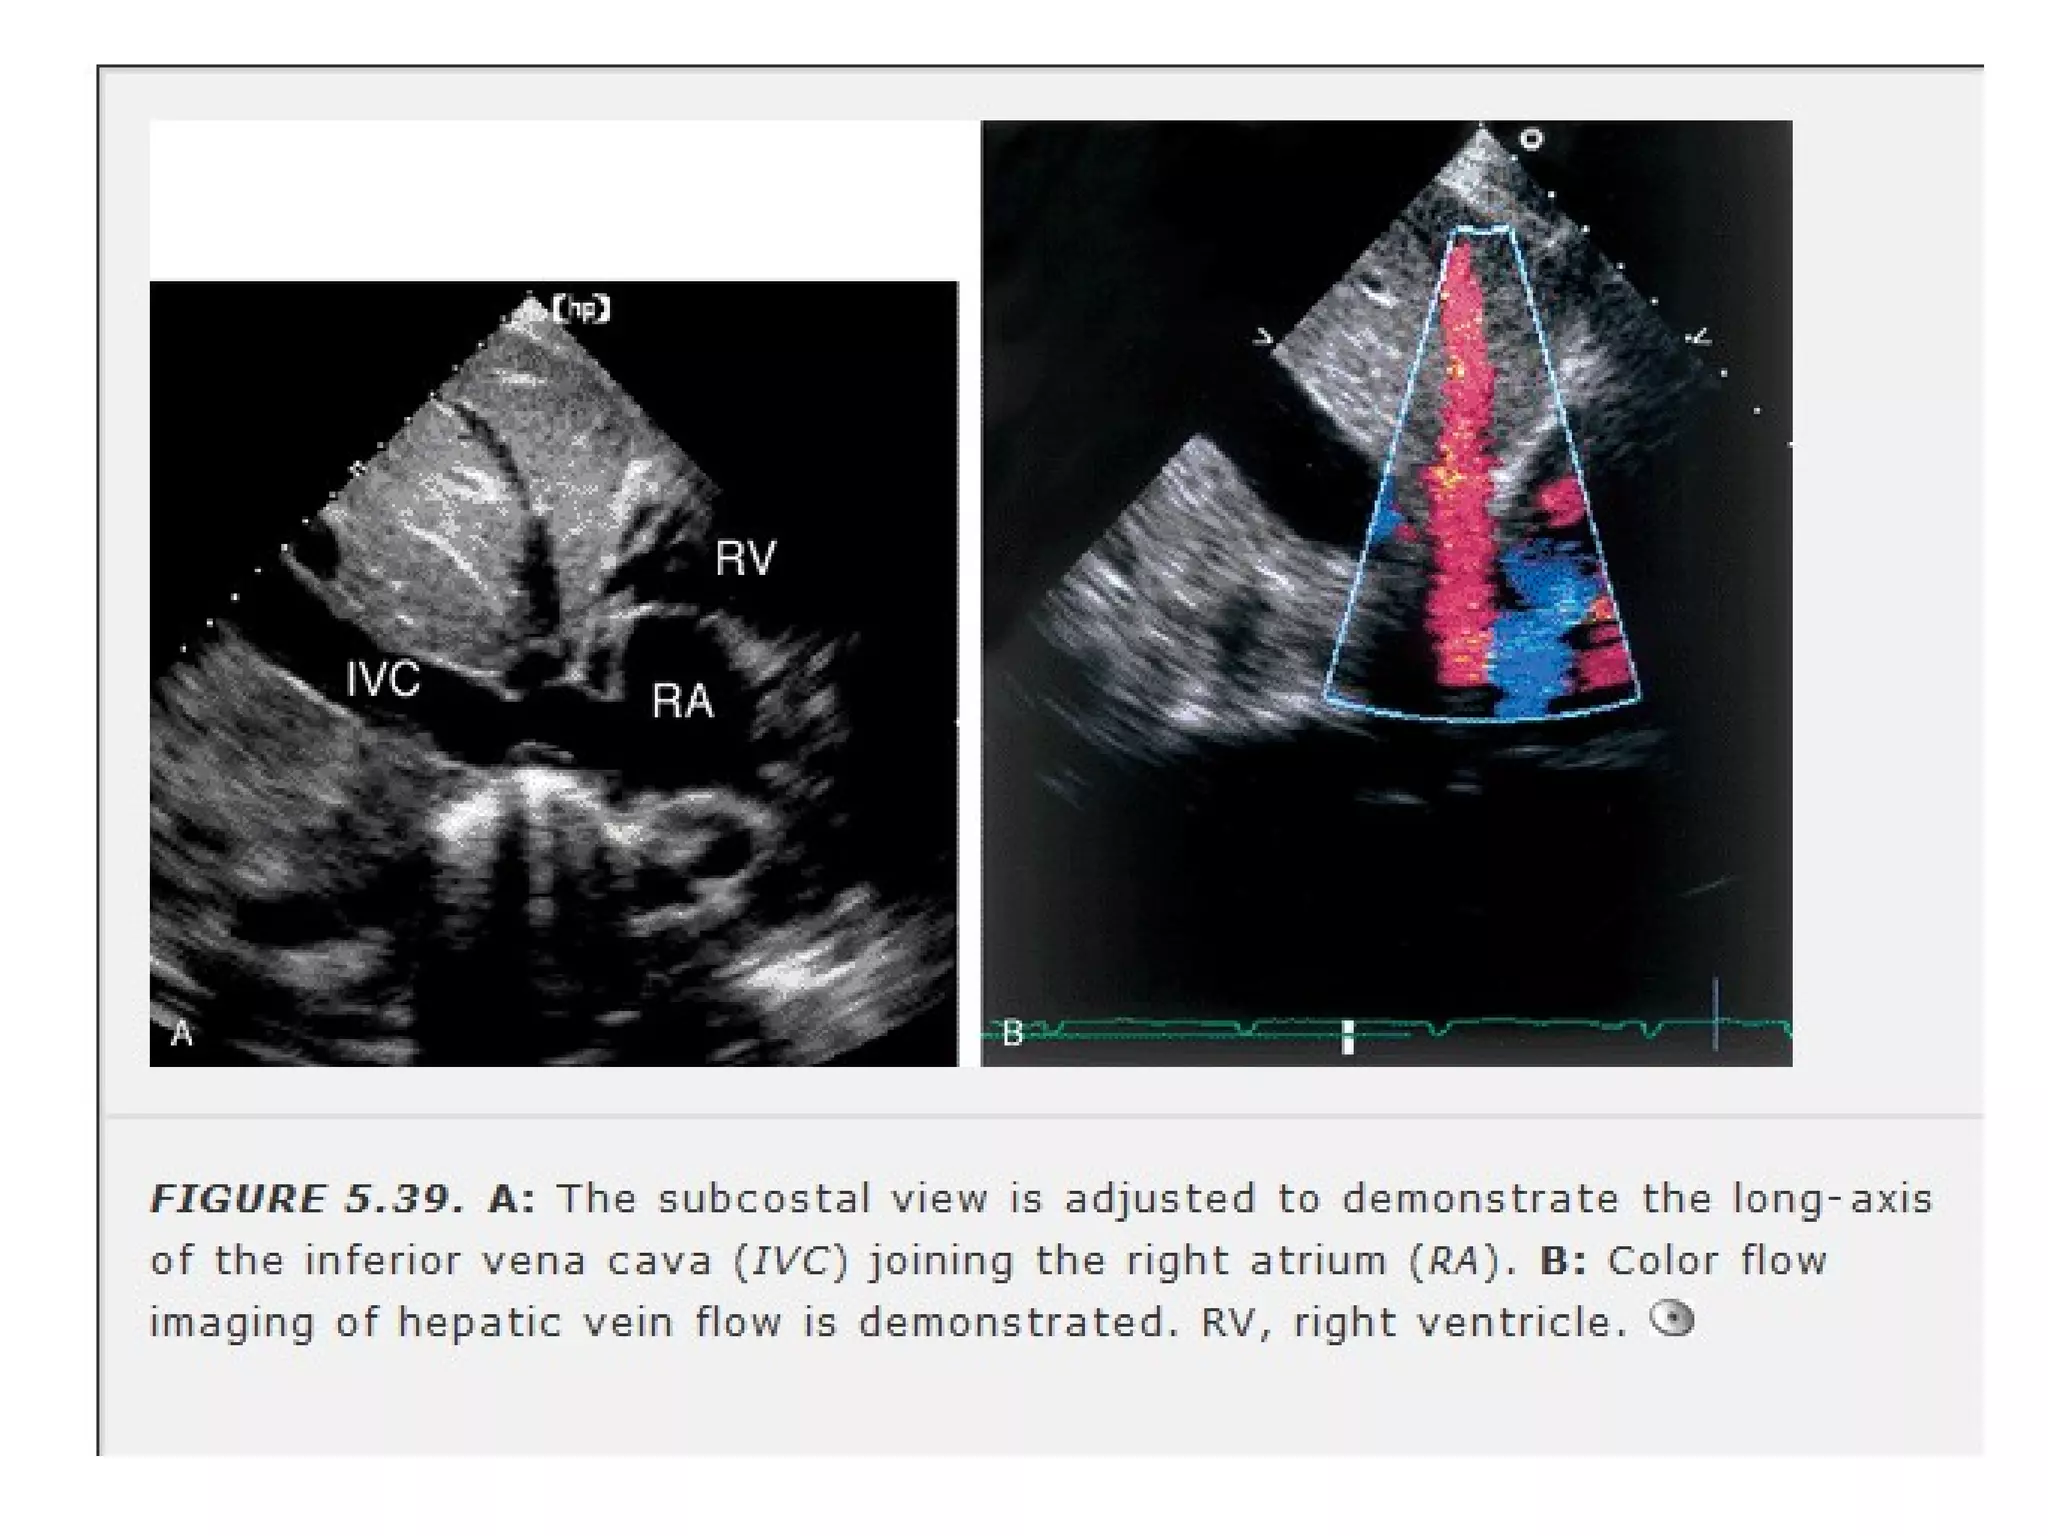

• 54.

• beam isoriented perpendicular to long axis of LV • better endocardial definition • septal defects are better delineated. • Only view that visualises superior portion of IAS • proximity of RV free wallto the transducer(pericardial tamponade) • IVC & hepatic veins are viewed.

• IVC & hepatic veins are viewed.

Far Posterior tilt to visualise pulmonary veins